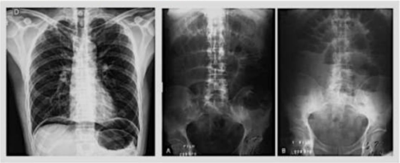

Paciente masculino, 30 anos, encaminhado a unidade de pronto atendimento de nível secundário devido a hipótese de abdome agudo obstrutivo por bridas. Queixa-se de dor abdominal súbita há 8 horas, intensa, em facada, em andar superior do abdome, associada a um episódio de vômito, com piora progressiva durante a observação, sem melhora com analgésicos. Nega trauma recente. Tem histórico de laparotomia prévia por ferimento de arma de fogo. Ao exame físico: regular estado geral, desidratado, taquicárdico, afebril. Semiologia cardiopulmonar normal. Abdome distendido, doloroso difusamente, tenso, com defesa involuntária à palpação. São realizadas as radiografias de abdome agudo abaixo: A melhora conduta para este caso é: